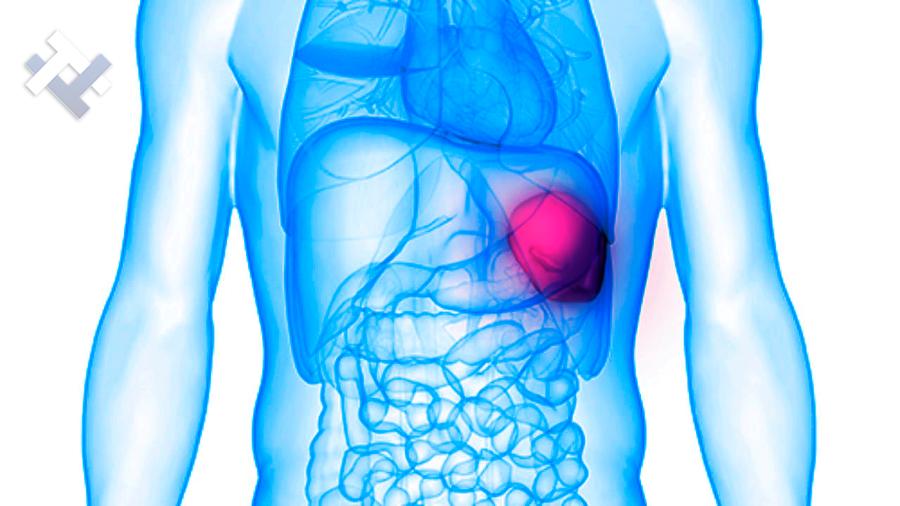

Ο Γενικός Χειρουργός Λιάγκος Γεώργιος MD PhD εκτελεί τις επεμβάσεις Λαπαροσκοπικά, Ενδοσκοπικά, Ανοιχτά Ελάχιστα Επεμβατικά και με Laser. Η θεραπεία εξατομικεύεται σε κάθε ασθενή ανάλογα με τις ανάγκες του. Αναλαμβάνει περιπτώσεις όπως κήλες και κοιλιοκήλες (αντιμετώπιση βουβωνοκήλης, αντιμετώπιση ομφαλοκήλης, θεραπεία επιγαστρικής κήλης, κήλη των αθλητών (Σύνδρομο κοιλιακών προσαγωγών), αντιμετώπιση μετεγχειρητικής κήλης, θεραπεία Μηροκήλης), πέτρες στη χοληδόχο κύστη, λαπαροσκοπική χολοκυστεκτομή, αντιμετώπιση Κύστη Κόκκυγος με λέιζερ (laser), παθήσεις πρωκτού, χειρουργική laser σύγχρονων κυκλικών ινών (αιμορροΐδες αντιμετώπιση, θεραπεία αιμορροϊδων με laser (LHP), αφαίρεση αιμορροΐδων με υπερήχους (HALL-RAR), χωρίς Χειρουργείο με ελαστικούς δακτυλίους (Τεχνική BARON-RBL), θεραπεία ραγάδας πρωκτού (Ραγάδα δακτυλίου), θεραπεία περιεδρικού συριγγίου, θεραπεία περιεδρικού αποστήματος, κονδυλώματα πρωκτού Θεραπεία, δερματικό ράκος (Skin tag) εκτομή, αντιμετώπιση Kνησμού, καρκίνος πρωκτού θεραπεία), παθήσεις Δέρματος, χειρουργική με laser CO2, αφαίρεση μορφωμάτων δέρματος - βιοψίες, αφαίρεση ελιάς (Σπίλου), σμηγματογόνος κύστης θεραπεία, αφαίρεση λιπώματος, είσφρυση όνυχος χειρουργείο, καρκίνος δέρματος θεραπεία, οξεία σκωληκοειδίτιδα, παθήσεις Λεπτού και Παχέος Εντέρου, ειλεός λεπτού εντέρου, εκκολπωμάτωση (Εκκολπωματίτιδα) σιγμοειδούς, καρκίνος παχέος εντέου, κολοστομίες, port χημειοθεραπείας κ.α.

Ο Γενικός Χειρουργός Λιάγκος Γεώργιος MD PhD εκτελεί τις επεμβάσεις Λαπαροσκοπικά, Ενδοσκοπικά, Ανοιχτά Ελάχιστα Επεμβατικά και με Laser. Η θεραπεία εξατομικεύεται σε κάθε ασθενή ανάλογα με τις ανάγκες του. Αναλαμβάνει περιπτώσεις όπως κήλες και κοιλιοκήλες (αντιμετώπιση βουβωνοκήλης, αντιμετώπιση ομφαλοκήλης, θεραπεία επιγαστρικής κήλης, κήλη των αθλητών (Σύνδρομο κοιλιακών προσαγωγών), αντιμετώπιση μετεγχειρητικής κήλης, θεραπεία Μηροκήλης), πέτρες στη χοληδόχο κύστη, λαπαροσκοπική χολοκυστεκτομή, αντιμετώπιση Κύστη Κόκκυγος με λέιζερ (laser), παθήσεις πρωκτού, χειρουργική laser σύγχρονων κυκλικών ινών (αιμορροΐδες αντιμετώπιση, θεραπεία αιμορροϊδων με laser (LHP), αφαίρεση αιμορροΐδων με υπερήχους (HALL-RAR), χωρίς Χειρουργείο με ελαστικούς δακτυλίους (Τεχνική BARON-RBL), θεραπεία ραγάδας πρωκτού (Ραγάδα δακτυλίου), θεραπεία περιεδρικού συριγγίου, θεραπεία περιεδρικού αποστήματος, κονδυλώματα πρωκτού Θεραπεία, δερματικό ράκος (Skin tag) εκτομή, αντιμετώπιση Kνησμού, καρκίνος πρωκτού θεραπεία), παθήσεις Δέρματος, χειρουργική με laser CO2, αφαίρεση μορφωμάτων δέρματος - βιοψίες, αφαίρεση ελιάς (Σπίλου), σμηγματογόνος κύστης θεραπεία, αφαίρεση λιπώματος, είσφρυση όνυχος χειρουργείο, καρκίνος δέρματος θεραπεία, οξεία σκωληκοειδίτιδα, παθήσεις Λεπτού και Παχέος Εντέρου, ειλεός λεπτού εντέρου, εκκολπωμάτωση (Εκκολπωματίτιδα) σιγμοειδούς, καρκίνος παχέος εντέου, κολοστομίες, port χημειοθεραπείας κ.α.